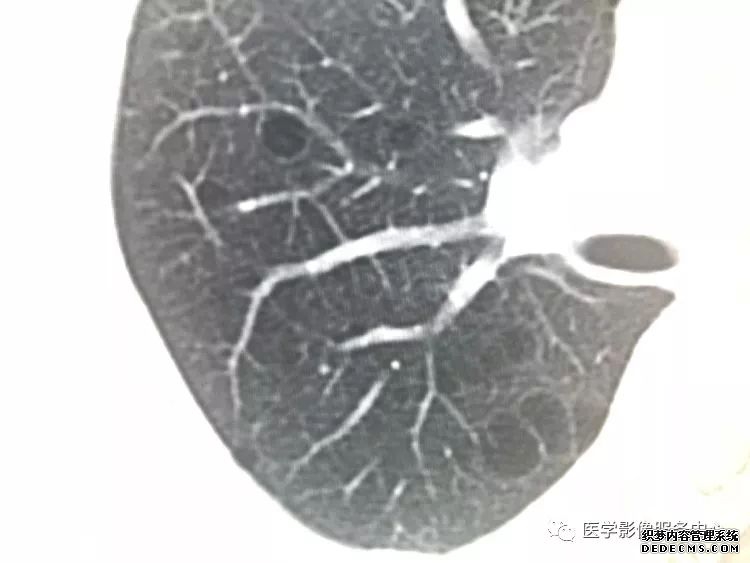

肺隔离症:易误诊为肺癌的占位性病变,肺穿刺禁忌!